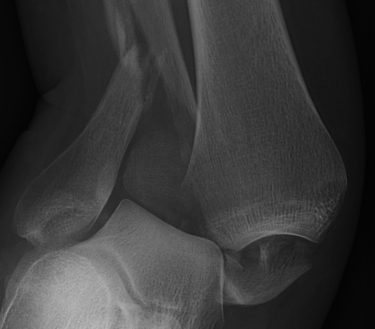

![]() |

Lateral talar shift / increased medial clear space / deltoid ligament injury

Tibia / fibular overlap < 1mm / syndesmotic injury